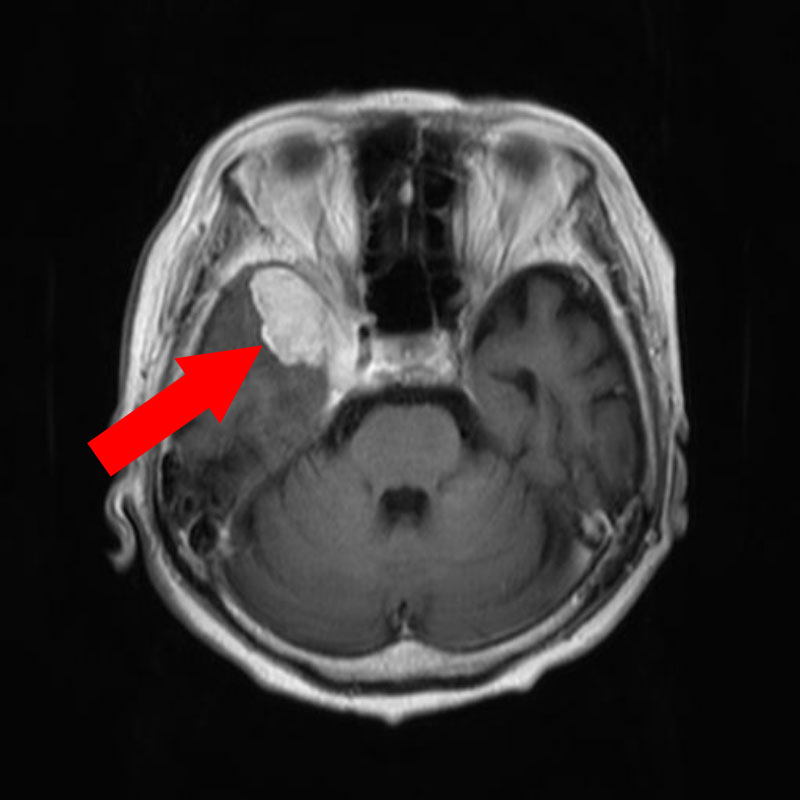

623

'25年4月

70代

聴神経腫瘍

頭蓋内腫瘍摘出術

No.’25_25 手術前1

No.’25_25 手術前2